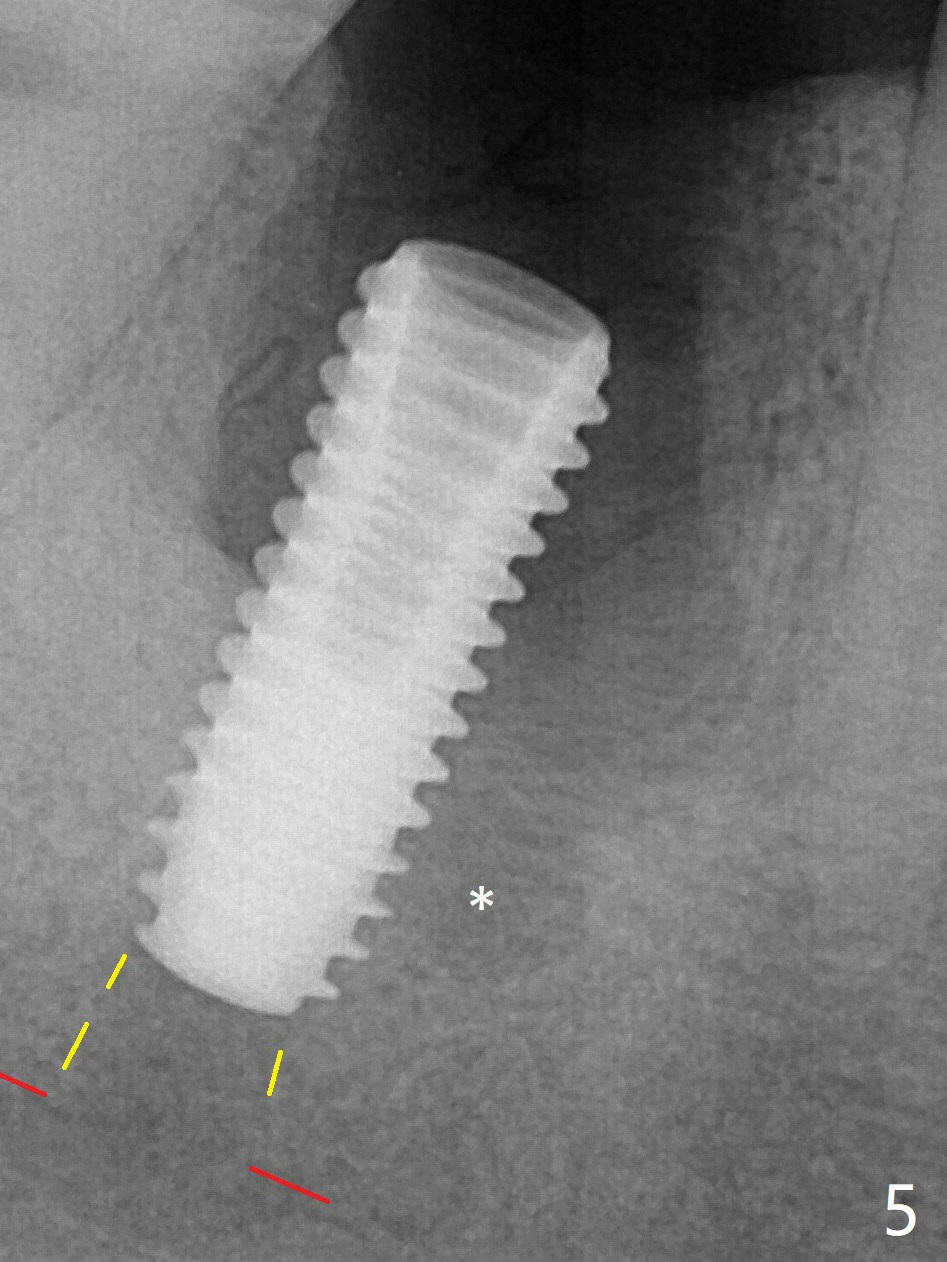

A 5x13 mm implant is placed superficially (Fig.5) with a trace of the previous osteotomy (yellow line) and deep space created by the mesial osteotomy (*). Red dashed line: the superior border of the Inferior Alveolar Canal. Apparently the pathological and iatrogenic defects are filled with allograft (Fig.6 *).